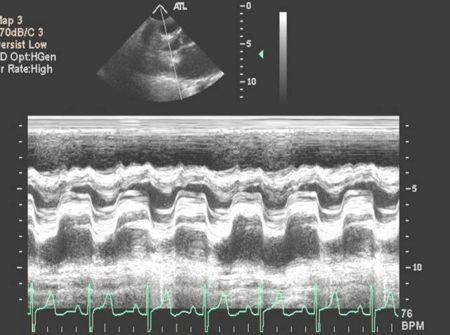

M Mode in Hypertrophic Cardiomyopathy

- Septal hypertrophy

- Systolic anterior motion (SAM) of the anterior mitral valve leaflet

- Mid-systolic (premature) closure of the aortic valve due to outflow track obstruction